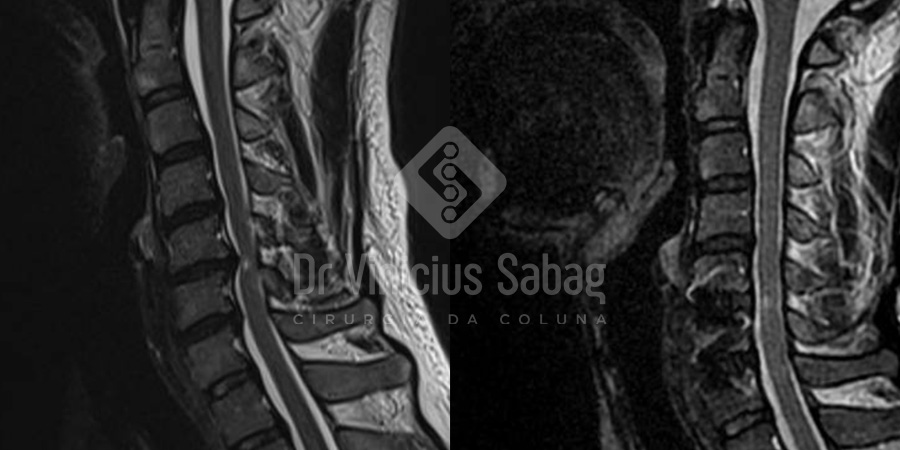

Foi realizada ressonância magnética pós-operatória, que demonstrou descompressão completa da medula espinhal, confirmando o sucesso do tratamento cirúrgico.

Ressonâncias magnéticas pré e pós-operatórias demonstrando descompressão completa da medula espinhal após o tratamento cirúrgico.